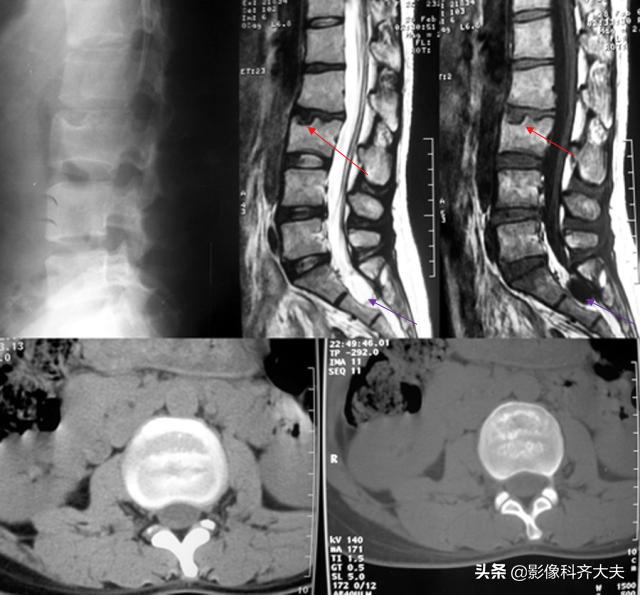

正侧位示腰4、5间隙变窄,CT扫描示腰4、5间盘突出

CT:椎间盘突出(中央型)

MRI:椎间盘突出(外侧型)

MRI:腰4、5间盘变性、突出,硬膜囊受压